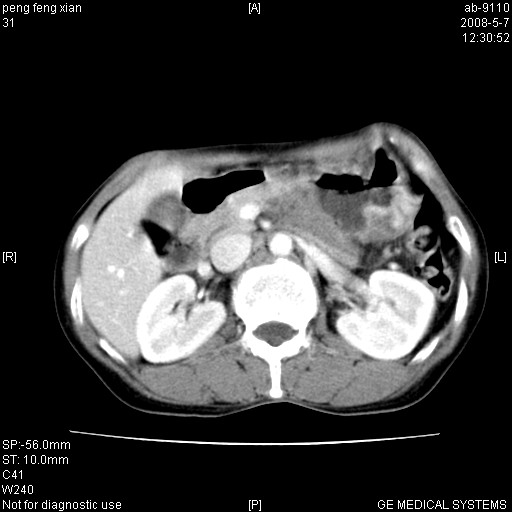

女,56岁。b超左一腹包块,考虑胃肠道肿瘤。

胃底占位待出;右肾结石?

胃体部胃壁增厚,不均匀性强化,与胰腺分解欠情.

考虑:胃癌,胰腺受侵待除外.